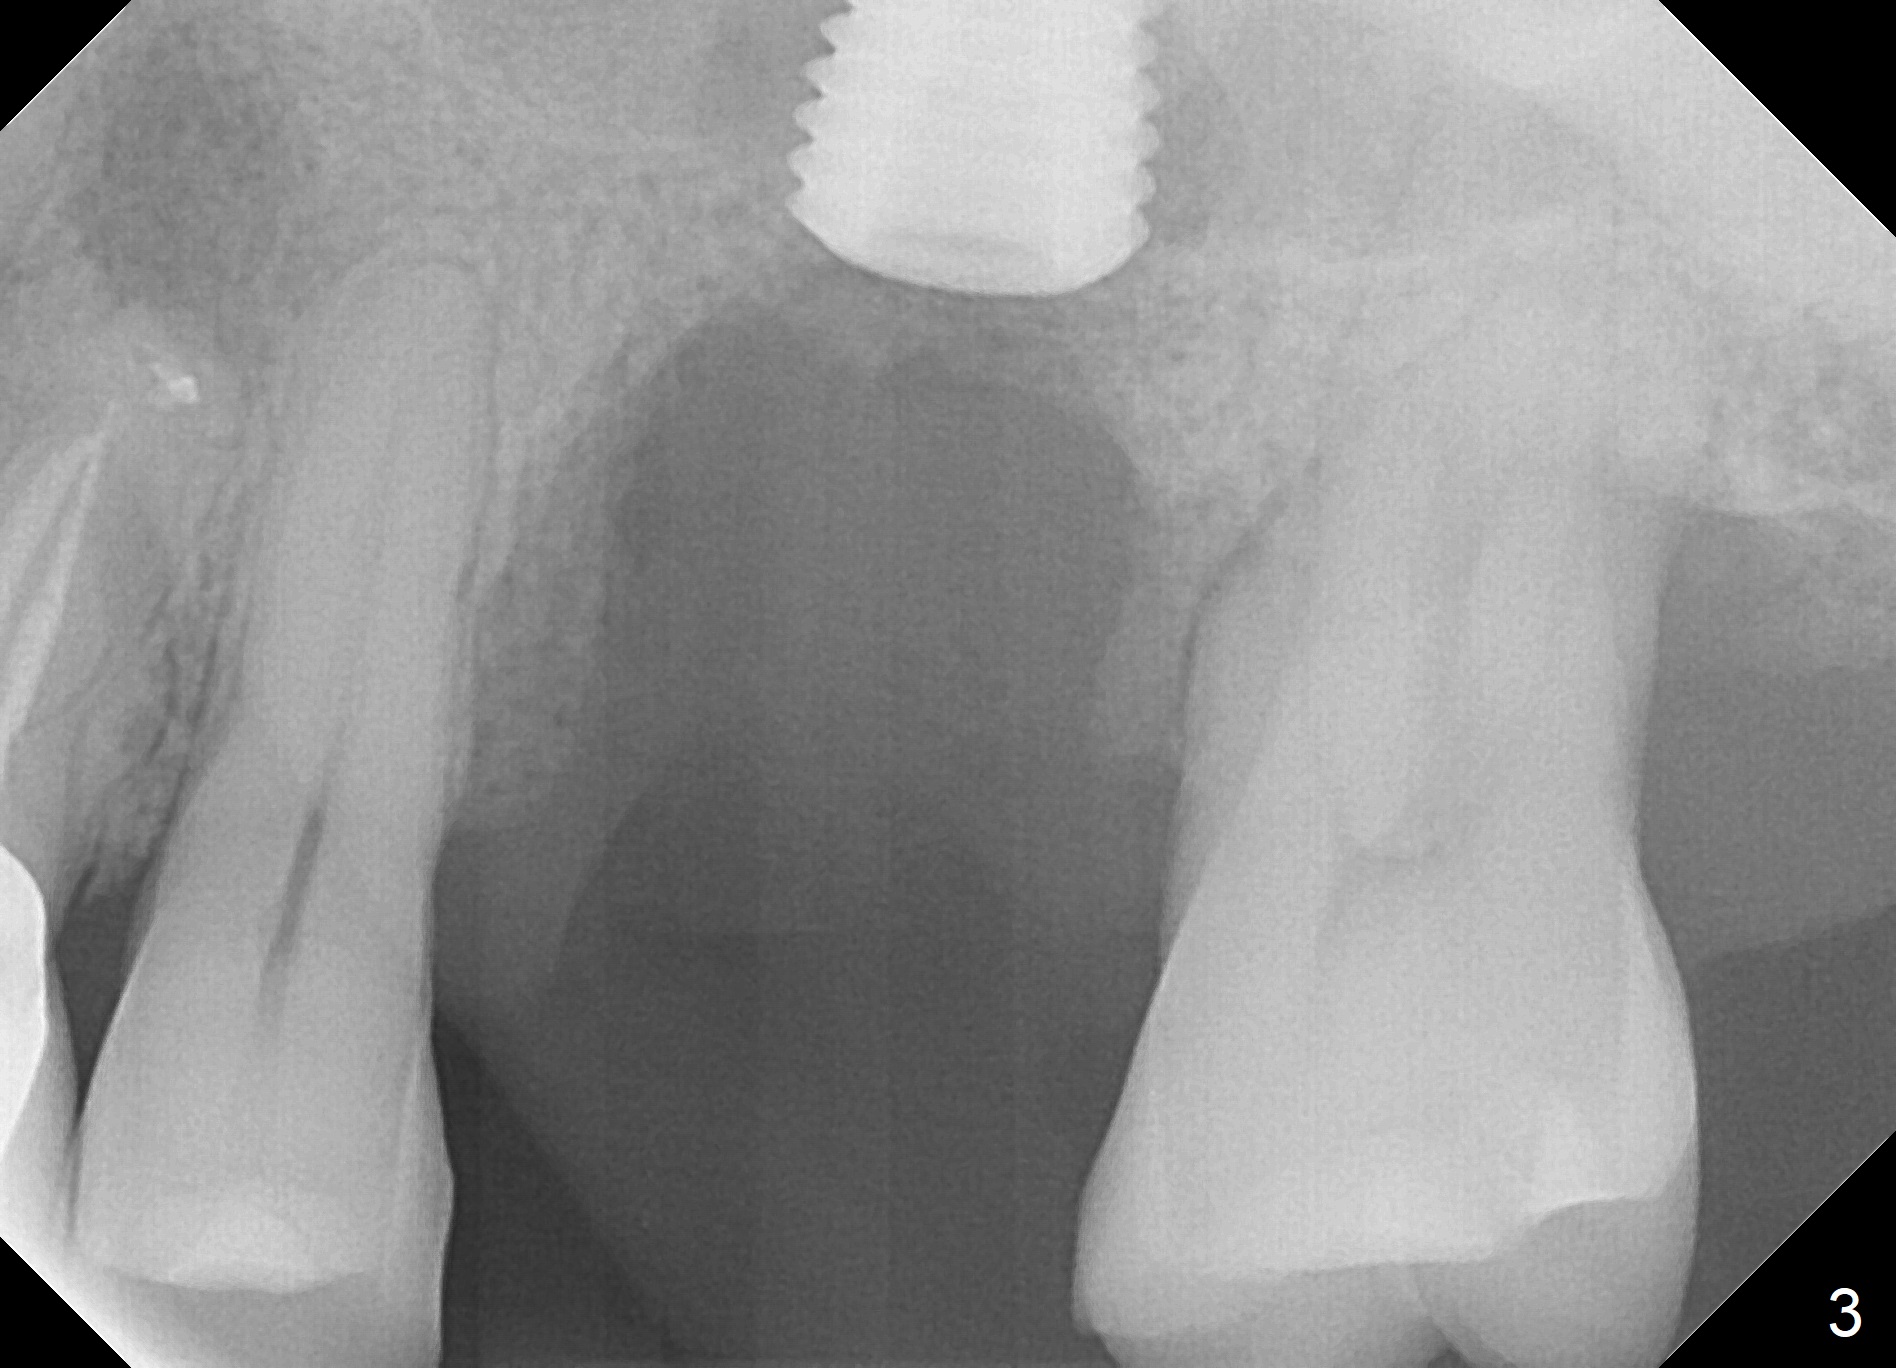

When the tooth #14 is extracted, the buccal plate is lost, while the apex of the palatal socket is perforated.  The palatal slope of the septum appears to be a suitable site for osteotomy, but the depth seems to be 2 mm.  After sequential osteotomy until 5.3 mm with drills, a 5.9 mm SM tap obtains stability (Fig.2).  A 5.9x8 mmm implant is placed with barely sufficient stability after 1 piece of PRF membrane and VeraGraft (Fig.2-4).  The implant rotates and dislodges when an abutment is being placed.  Neither do 6-8x17 mm Tatum taps achieve primary stability.  Socket preservation is performed, followed by periodontal dressing (Fig.5).  Primary stability might have been obtained if a smaller IBS implant with fins were placed in the palatal socket.  The periodontal dressing has dislodged 1 week postop; the socket appears healing (Fig.6,7).  Bone graft seems to be minimal or bone density of the graft is low (Fig.8).  The socket heals with a wide ridge 2 months post socket preservation, but the tooth #15 seems to be buccal (Fig.9) and mesial (Fig.10) shift.  After use of Magic Split and Expanders (until 3.8 mm for 13 mm), try 5 mm dummy implant (Fig.11).  If 6 mm one fails to achieve stability substantially, switch to 7 mm Tatum tapered tap provided there is enough mesiodistal space (use 8 mm implant positioner to gauze the space beforehand (preop)).  Consider using Vanilla (not Vera) Graft to fill in the gap between implant and osteotomy.  When primary stability is obtained, place a nonfunctional provisional to prevent further shifting (Fig.11 white outline).  After osteointegration, use the provisional (reline and separator) to distalize the tooth #15.